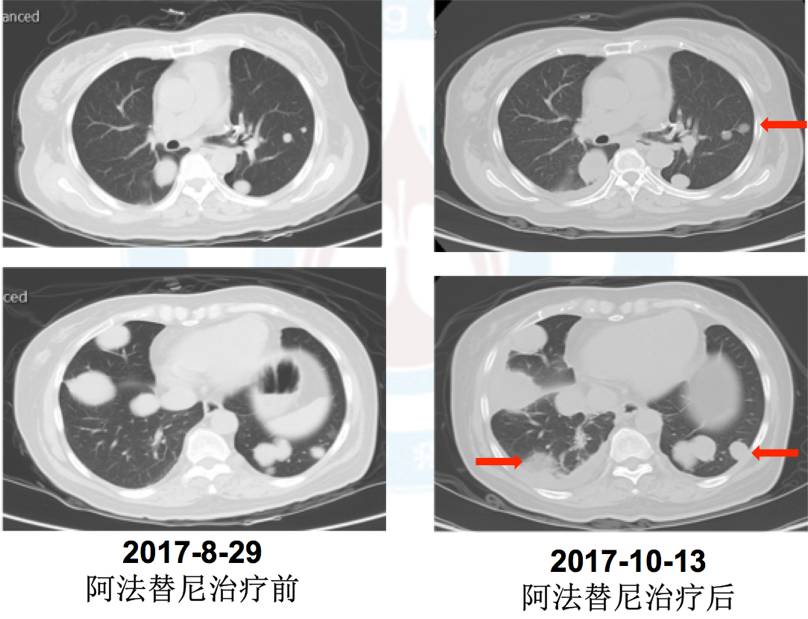

5.五线:2017年9月5日阿法替尼40mg靶向治疗,治疗1周出现I度皮疹、消化道反应,治疗45天疗效评价PD(混合疗效,部分缩小)。